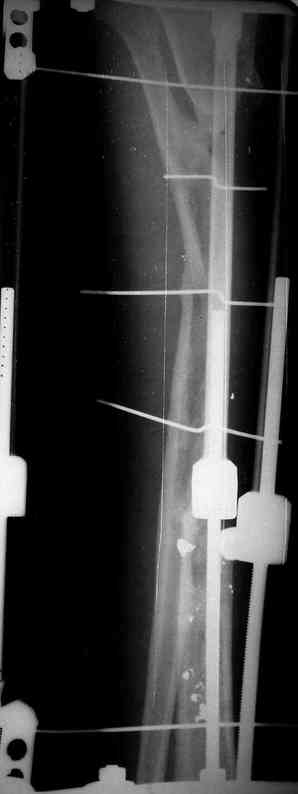

Re: case tibial defect

Я думал, что в нижнем отделе голени без мягкотканнего покрытия будет сложно проведения тибиализацию, но твой пример показывает - метод работает даже в таких трудных условиях.

Кстати, как метод использования малоберцовой при дефектах на более высоком отделе большеберцовой, недавно с моим партнерем опубликовали в главе по замещению дефектов в книжке Роберта Росбруха и Светланы Илизаровой по Наружным Фиксаторам.

Правда те мои случаи были сделаны давно, еще в Латинской Америке, и конечно качество исполнения отстает от идеалов, но, несмотря на отсутствие нормальных спиц с упором, метод сработал в свое время.

Приходилось встречать замещенные дефекты малоберцовой костью без применения метода Идизарова, и при соблюдении осторожности хрупкая малоберцовая за короткое время под вождействием нагрузки утолщались в диаметре.